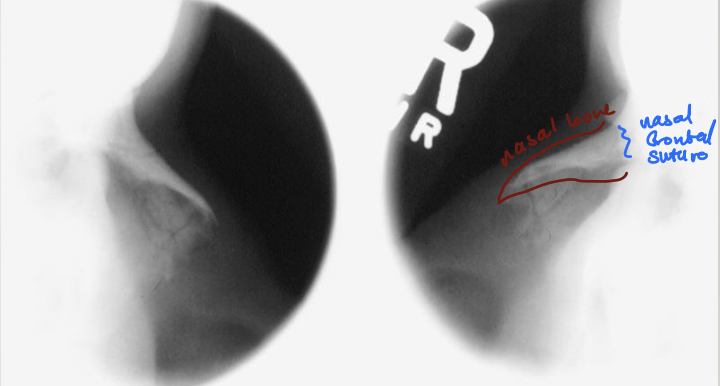

what is this projection

lateral nasal bones

IPL perp

MSP parallel

CR perp, ½ “ inferior nasion